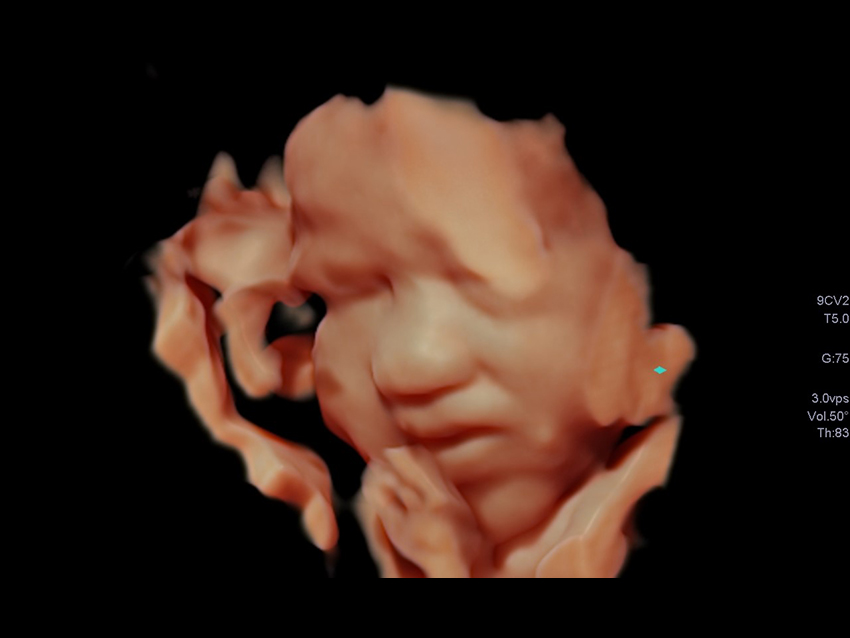

Удосконалені інструменти візуалізації, такі як 3D/4D luminance додають обличчю плода реалістичного вигляду.

Індикації в акушерстві з підтримкою алгоритму глибокого навчання* допомагають ідентифікувати стандартні анатомічні структури для пришвидшення робочого процесу та посилення рівномірності результатів обстеження.

Технологія Advanced Dynamic Flow (ADF) підтримує просторову та часову роздільну здатність за допомогою короткоімпульсної доплерівської візуалізації, що забезпечує гемодинамічну оцінку серця плода з високою роздільною здатністю.